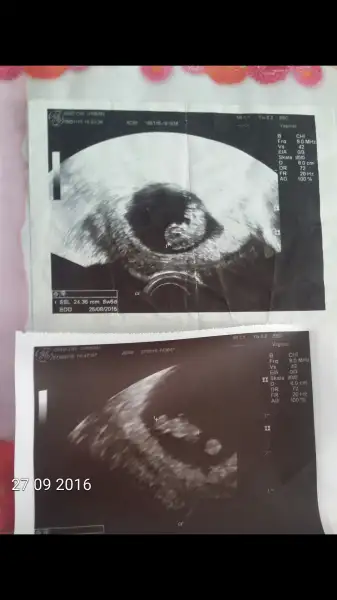

Slvesrer bide bana yorum yap kiz cokk heycanlii :)) yukardaki kizimin resim 8 haftalar asagudaki simdiki bebis 7 haftalik ikiside vajinal biri saga biri sola dayanmis ama ikisinin kafa solda sanki ? Sen ne diyorsun ?? Bi zahmet fikrini alayim :)

• Screenshot_2016-09-27-18-40-25.webp

Screenshot_2016-09-27-18-40-25.webp

9,4 KB · Görüntüleme: 268

Sen Slvestera sormussun ama benim bir fikrim var soylesem olur mu? Ilk bebegini pek anlamadim ama ikincisinde gorunen yusyuvarlak sey yolk sac sanirsam ve de saga yakin (plasentaya da ayni zamanda). Ramzi teorisi bebisin erkek diyor, valla ben degil:) belli olunca bak bi tutuyor mu,ki ins gonlune gore olsun ve sanirm erkek istiyorsun degil mi?